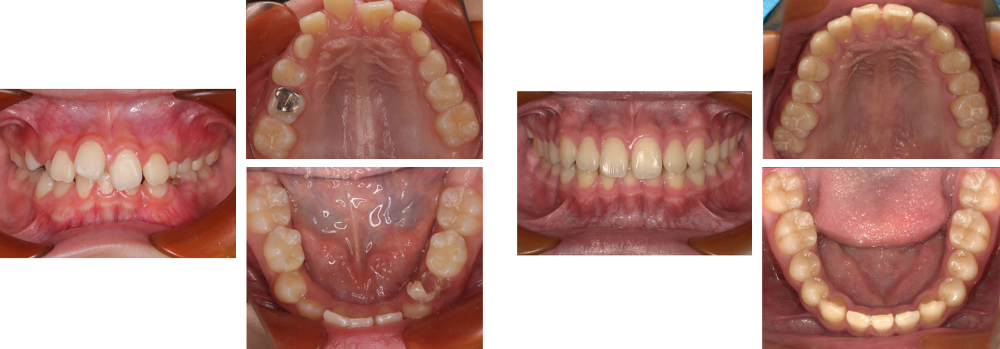

小児矯正

術前

術後

| 治療内容 | 叢生に対して床矯正・ブラケットを使用し治療を行った |

|---|---|

| 治療期間・回数 | 40カ月間・37回(動的治療まで) |

| 費用 ※自由診療となります |

矯正検査①:33,000円 床装置(ネジあり):77,000円 ×4 ブラケット:198,000円 ×2 |

| リスク・副作用 |

|